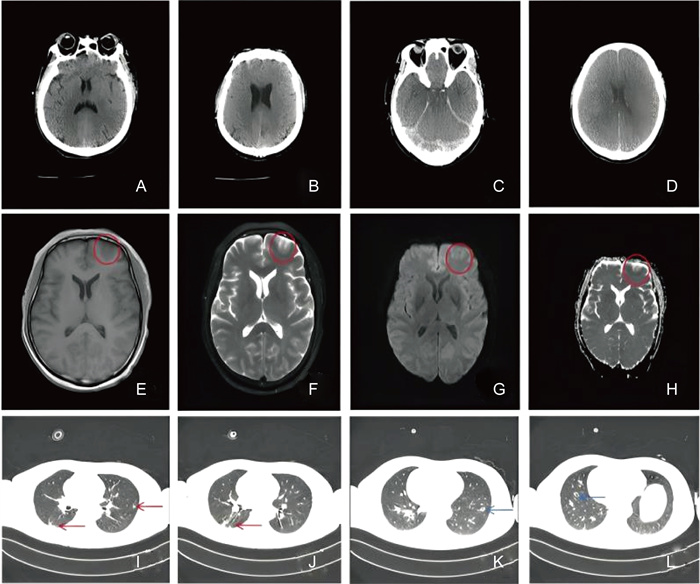

1 病例特点患者为51岁男性,因“头痛10余天”于2023年7月21日就诊于该院。患者既往有“2型糖尿病”病史,家属代诉可疑鸟粪接触史。10余天前患者无明显诱因出现头痛,疼痛部位位于左侧颈枕部及额顶部,呈持续性胀痛,体位变化加重,疼痛未向他处放射,并有一过性失语、间歇性跛行,先就诊于省级医院外科系统完善颈椎计算机断层成像(computed tomography,CT)提示:颈椎退行性变;C4/5椎间盘膨出;项韧带钙化。头颅磁共振成像(magnetic resonance imaging,MRI)和磁共振血管造影(magnetic resonance angiography,MRA)未见异常,患者遂来该院门诊并被收入疼痛科进一步治疗。入院查体生命体征平稳,神志清楚,颈软,定向力正常,双下肢肌力Ⅳ级,浅感觉减弱,完善颈椎MRI提示颈4/5椎间盘突出(右旁中央型),相应脊髓少许变性可能,考虑“颈椎病、脊髓压迫”,遂于2023年7月24日全麻下行“前路颈4/5椎间盘髓核摘除、椎管减压、零切迹椎间融合器植骨融合术”,术后第2天患者头痛无明显好转,并出现谵妄,自行拔除尿管及心电监护,请神经内科会诊考虑颅内感染,并转入神经内科治疗,完善腰椎穿刺检查,脑脊液压力280 mmH2O,脑脊液常规及生化结果提示白细胞295×106/L,以多核细胞为主,总蛋白2 341 mg/L,葡萄糖9.0 mmol/L,氯132.2 mmol/L;完善病原学检测,结果提示脑脊液中隐球菌荚膜抗原阳性(7月25日),墨汁染色涂片找到新型隐球菌(7月25日,见图 1),脑脊液二代测序(metagenomic next generation sequencing,mNGS)检测提示新型隐球菌(7月25日,见图 2),血培养回报培养出新型隐球菌(7月26日,见表 1),同时完善胸部CT提示双肺多发肺结节、空洞(见图 3I~L),不排除隐球菌病变,结合上述病史、体征及辅助检查结果,考虑隐球菌肺炎合并脑膜炎可能性大,经抗感染、脱水降颅压、镇静等对症支持治疗,病情仍在进展,遂于7月25日转入重症监护病房(intensive care unit,ICU)。转入ICU后查体患者意识呈浅昏迷,双侧瞳孔等大等圆,直径约3.5 mm,对光反射迟钝,双侧克氏征阳性,病理征阴性。立即予哌拉西林/他唑巴坦+氯康唑+两性霉素B胆固醇硫酸酯复合物(因氟胞嘧啶需临购暂未用)抗感染、脑保护、脱水降颅压等治疗,转入后第2天患者的意识障碍仍呈进行性加重,深浅反射消失,血氧饱度、心率下降,考虑其颅内压进行性升高,遂行气管插管连接呼吸机辅助通气,加用氟胞嘧啶联合两性霉素B脂质体抗真菌治疗,予腰大池引流缓解脑脊液压力。经上述治疗后患者的意识仍无改善,复查头颅CT后提示弥漫性脑肿胀并脑疝形成(7月27日,见图 3 C和D),出现中枢性尿崩症、凝血功能障碍、先后行双侧去骨瓣减压术+硬脑膜修补术、侧脑室引流,但患者仍处于深昏迷,血压需大剂量血管活性药物维持,2023年8月2日家属要求出院。

| 显示广泛的荚膜发育和子细胞的特征性出芽。 Extensive capsule development and characteristic budding of daughter cells showed. 图 1 新型隐球菌细胞的印度墨水染色 Fig. 1 India ink stain of Cryptococcus neoformans cells |